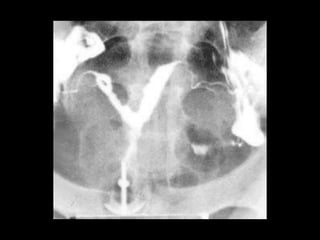

Ultrasonido que muestra siameses unidos por

el tórax: planteando la necesidad de practicar

un aborto

Ultrasonido que muestrasiameses unidos por el tórax: planteando la necesidad de practicar un aborto